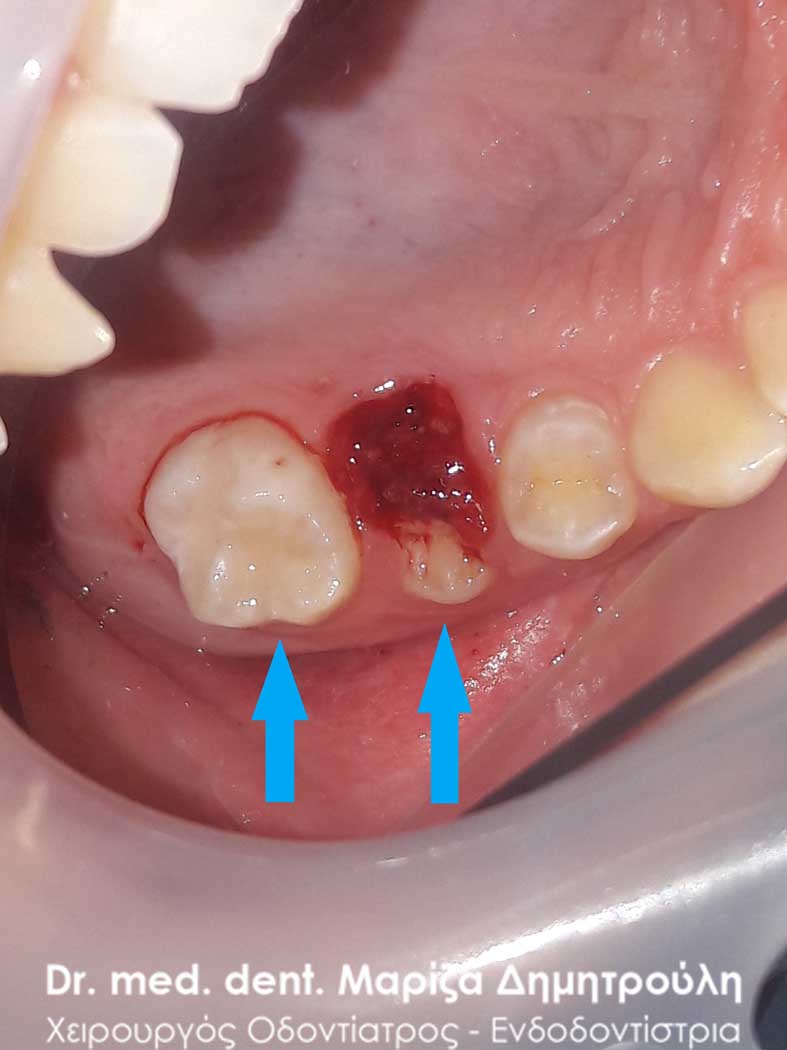

Στο συγκεκριμένο περιστατικό που παρουσιάζεται ο νεογιλός κυνόδοντας παρέμενε στη θέση του, ενώ ταυτόχρονα είχε ανατείλει ο μόνιμος κυνόδοντας. Μετά την αναγκαία εξαγωγή του νεογιλού δοντιού διαπιστώθηκε οτι δεν υπήρξε καμία φυσιολογική απορρόφηση της ρίζας του δοντιού με αποτέλεσμα το δόντι να παραμένει παραπάνω από το φυσιολογικό στο στόμα. Μετά την αφαίρεση του δοντιού ο μόνιμος κυνόδοντας πήρε την τελική φυσιολογική θέση σε διάρκεια ενός μηνός.

Περιστατικό – Εξαγωγή παιδικού δοντιού (διπλό δόντι / παραμονή νεογιλού δοντιού)

Η μαμά του μικρού νεαρού είχε τρομάξει καθώς τα δοντάκια του παιδιού της τον τελευταίο καιρό παρουσιάζουν την παρακάτω εικόνα που δείχνουν οι φωτογραφίες. Το πρόβλημα βέβαια ήταν πολύ απλό, καθώς για τη λύση του προβλήματος απαιτούταν μόνο η εξαγωγή των παιδικών δοντιών. Στην πραγματικότητα κάτω από τα παιδικά δοντάκια είχαν ήδη ανατείλει τα μόνιμα δόντια, τα οποία πίεζαν από κάτω τα αντίστοιχα παιδικά δοντάκια. Για αυτό το λόγο φαίνεται οι νεογιλοί τομείς να είναι στον αέρα. Το αισθητικό πρόβλημα αντιμετωπίστηκε άμεσα με την εξαγωγή των παιδικών δοντιών.

Περιστατικό – Εξαγωγή παιδικού δοντιού (διπλό δόντι / παραμονή νεογιλού δοντιού)

Οι γονείς του μικρού ασθενή τρόμαξαν καθώς αντίκρυσαν ένα επιπλέον δόντι στο στόμα του παιδιού τους. Η λύση ήταν απλή καθώς το μόνο που χρειαζόταν ήταν η εξαγωγή του παιδικού δοντιού, ώστε το αντίστοιχο νεογιλό να πάρει την τελική του θέση μέσα στο στόμα του παιδιού. Σε διάστημα ενός μηνός το παιδικό στόμα θα έχει μία φυσιολογική εικόνα με το μόνιμο δόντι να έχει κατέβει στη θέση του.